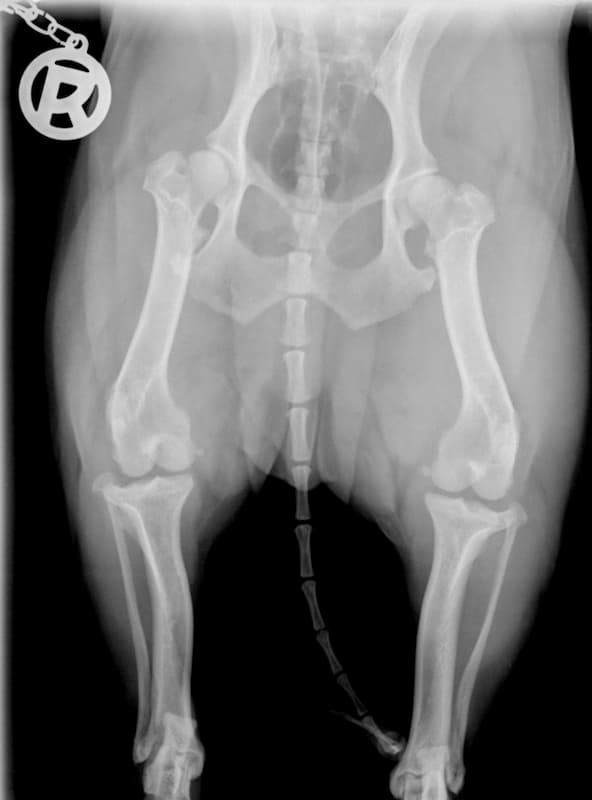

BARFen bei Erkrankungen des Bewegungsapparates

Es gibt eine Vielzahl von Beschwerden, die den Bewegungsapparat bei Hunden betreffen – am häufigsten handelt es sich um Erkrankungen oder Beschwerden der verschiedenen Gelenke, aber auch Bänder und Sehnen.

Je nach Art der Beschwerden und Ausprägung gibt es verschiedene Ansätze zur Behandlung, sowohl aus medizinischer als auch physiotherapeutischer Sicht.